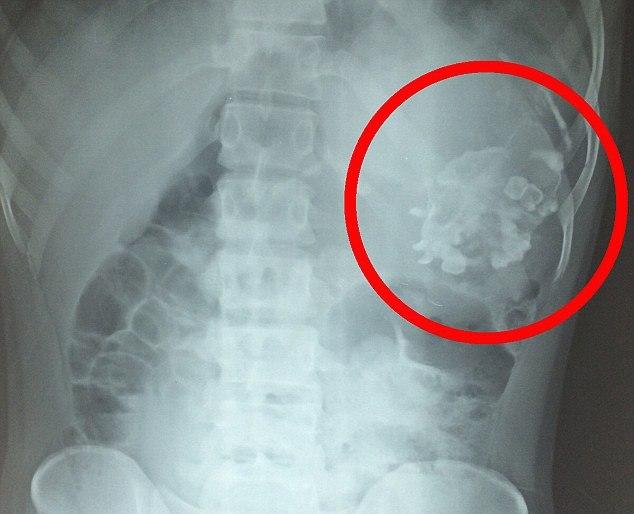

gif_animation インドにて、お腹が痛いと病院を訪れた18歳の少年の体から、”一緒に生まれてくるはずだった双子(であったもの)” が摘出されたそう。いわゆる「寄生胎児」と呼ばれるもので、その確率は500万人に1人とも言われているそう。[6]images